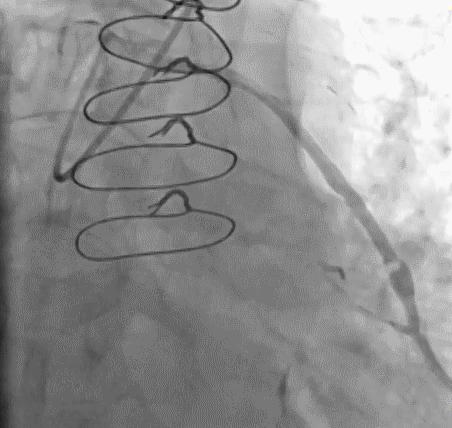

2.安全方面考虑

(1)导管总进圆锥动脉

➢ CASE 8

必要时更换导管,避免并发症的发生

(2)口部病变

应换短头、小号导管,轻柔少量注射对比剂